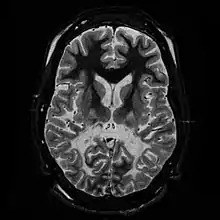

Leucodystrophie

Les leucodystrophies sont des maladies rares caractérisées par un processus de changement démyélinisation du système nerveux central et périphérique, d'apparence primitive et non inflammatoire et aboutissant à une sclérose cérébrale. Ce sont presque exclusivement des maladies génétiques.

Le terme de leucodystrophie se rapporte à un groupe de maladies d'origine génétique affectant la myéline du système nerveux central. La myéline constitue la substance blanche du cerveau et de la moelle épinière. Elle enveloppe la fibre nerveuse de la même manière que l'isolant plastique d'un câble électrique : c'est elle qui permet la bonne conduction des messages nerveux. Dans les leucodystrophies, cette myéline peut avoir des problèmes pour se former ou pour se maintenir (parfois, on remarque une démyélinisation).